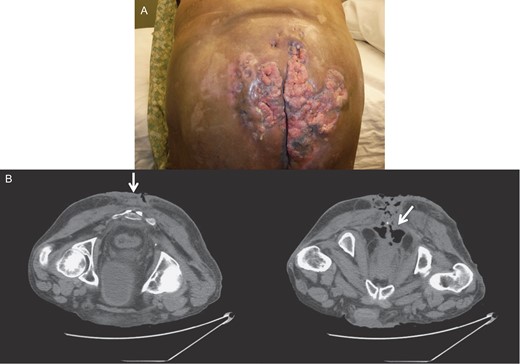

However, ~6 weeks later, he was readmitted due to regrowth of the invasive anal condyloma. All of the areas previously quiescent and clean of tumor were full of new lesions, extending into the pelvic sidewall and the anorectal region, as well as the area of excision. The lesions deteriorated with necrosis, foul odor, and abscesses over time, and debridement and drainage were performed mostly to manage the wound and reduce septic risk (Fig. 4). Multiple readmissions for secondary infections and peri-lesion abscesses occurred for months.

Gross image (A) and CT of the pelvis and perineum (B) showing tumor recurrence.